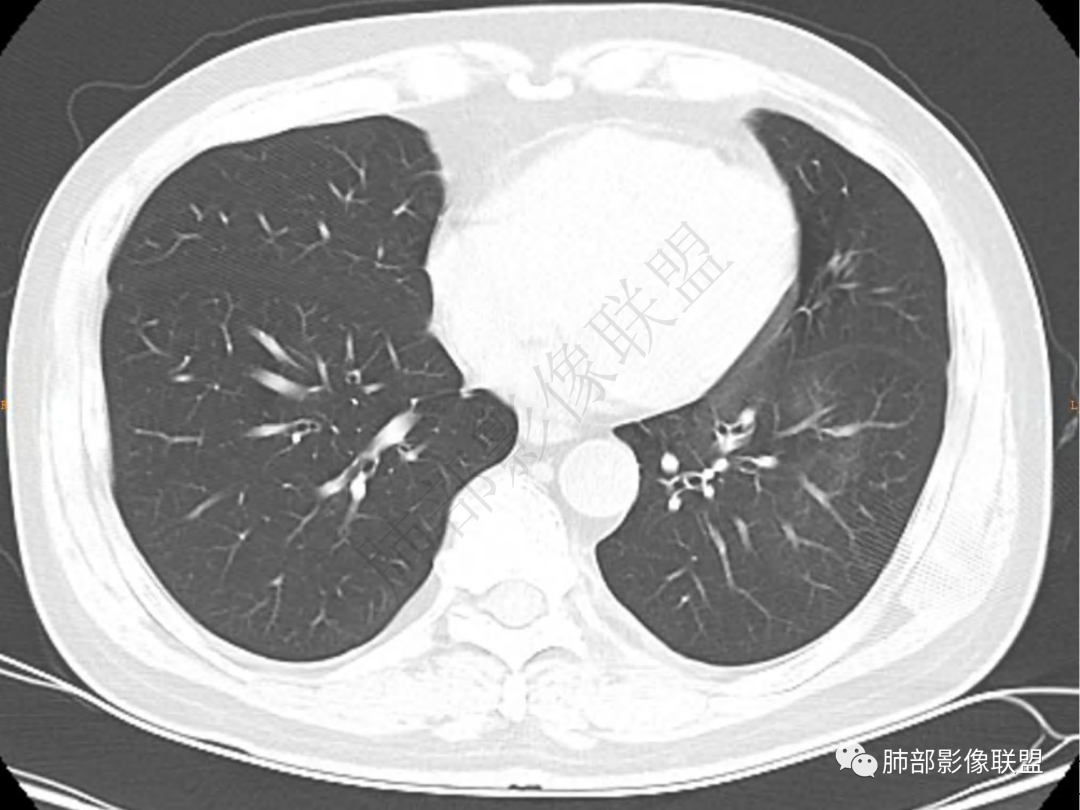

2.左肺下叶团片影,跨背段及内前基底段,实性部分类椭圆形,密度不甚均匀,可见毛刺及棘状突起,未见典型分叶及胸膜凹陷。病灶上下缘可见相应肺段支气管旁进侧出,管壁轻度增厚,未见狭窄阻塞。

3.周边较大范围磨玻璃影,边界相当模糊,小叶增厚明显。注意叶裂另一侧、左肺舌段亦可见磨玻璃影及增厚的小叶间隔。未见明确卫星病灶。

1.病灶不够密实,没有典型分叶,收缩乏力等,支气管未见截断等,缺乏一般肿瘤性肿块特征。

2.周围磨玻璃影边界不清缺乏限制,甚至“激惹”到相邻肺叶,也许提示较明显的炎性水肿。